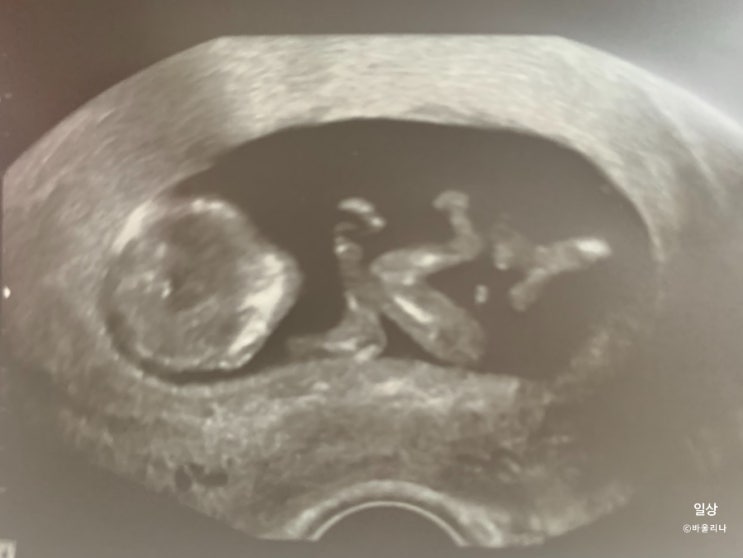

임신 16주차 증상 2차 기형아 검사 성별확인